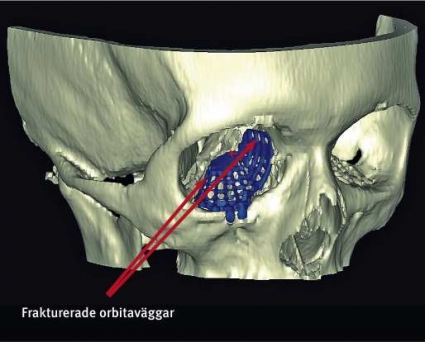

En 53-årig kvinna föll ner för en trappa, slog sig i ansiktet och ådrog sig högersidiga orbitafrakturer. Preoperativt fanns inget dubbelseende eller enoftalmus, däremot smärta i ögat vid blickriktning uppåt och lateralt. Preoperativ datortomografi visade en ren blow-out-fraktur av orbitabotten och medialväggen (Figur 2). Defekterna involverade större delen av orbitabotten ända bak till orbitans apex samt den mediala orbitaväggen upp till sutura frontoethmoidalis. Volymbestämning gjordes i mjukvaran Osirix efter att orbitans begränsningar markerats på alla axiala snitt mellan orbitans övre och nedre begränsning (60 snitt). Den skadade sidan uppmättes till 31,3 cm3, att jämföra med den friska sidans 26,0 cm3.

Patienten opererades 14 dagar efter skadan. Orbitan frilades transkonjunktivalt och bikoronart, med 360 graders lösning av periorbitan från orbitans benväggar, koagulering och delning av arteria ethmoidale anterior respektive fissura orbitalis inferior. Ett kombinerat anatomiskt implantat för orbitabotten och medialvägg fördes in via den nedre friläggningen och fixerades med skruvar mot margo infraorbitalis. Operationstiden var 170 minuter och blödningen ca 150 ml. Postoperativ datortomografiundersökning visade att man med implantatet uppnått en i stort sett fullständigt korrekt anatomisk rekonstruktion av orbitans benväggar. Implantatet återskapade bla konvexiteten långt bak medialt i orbitan (posterior bulge) på ett sätt som är mycket svårt att åstadkomma med andra typer av implantat (Figur 3).